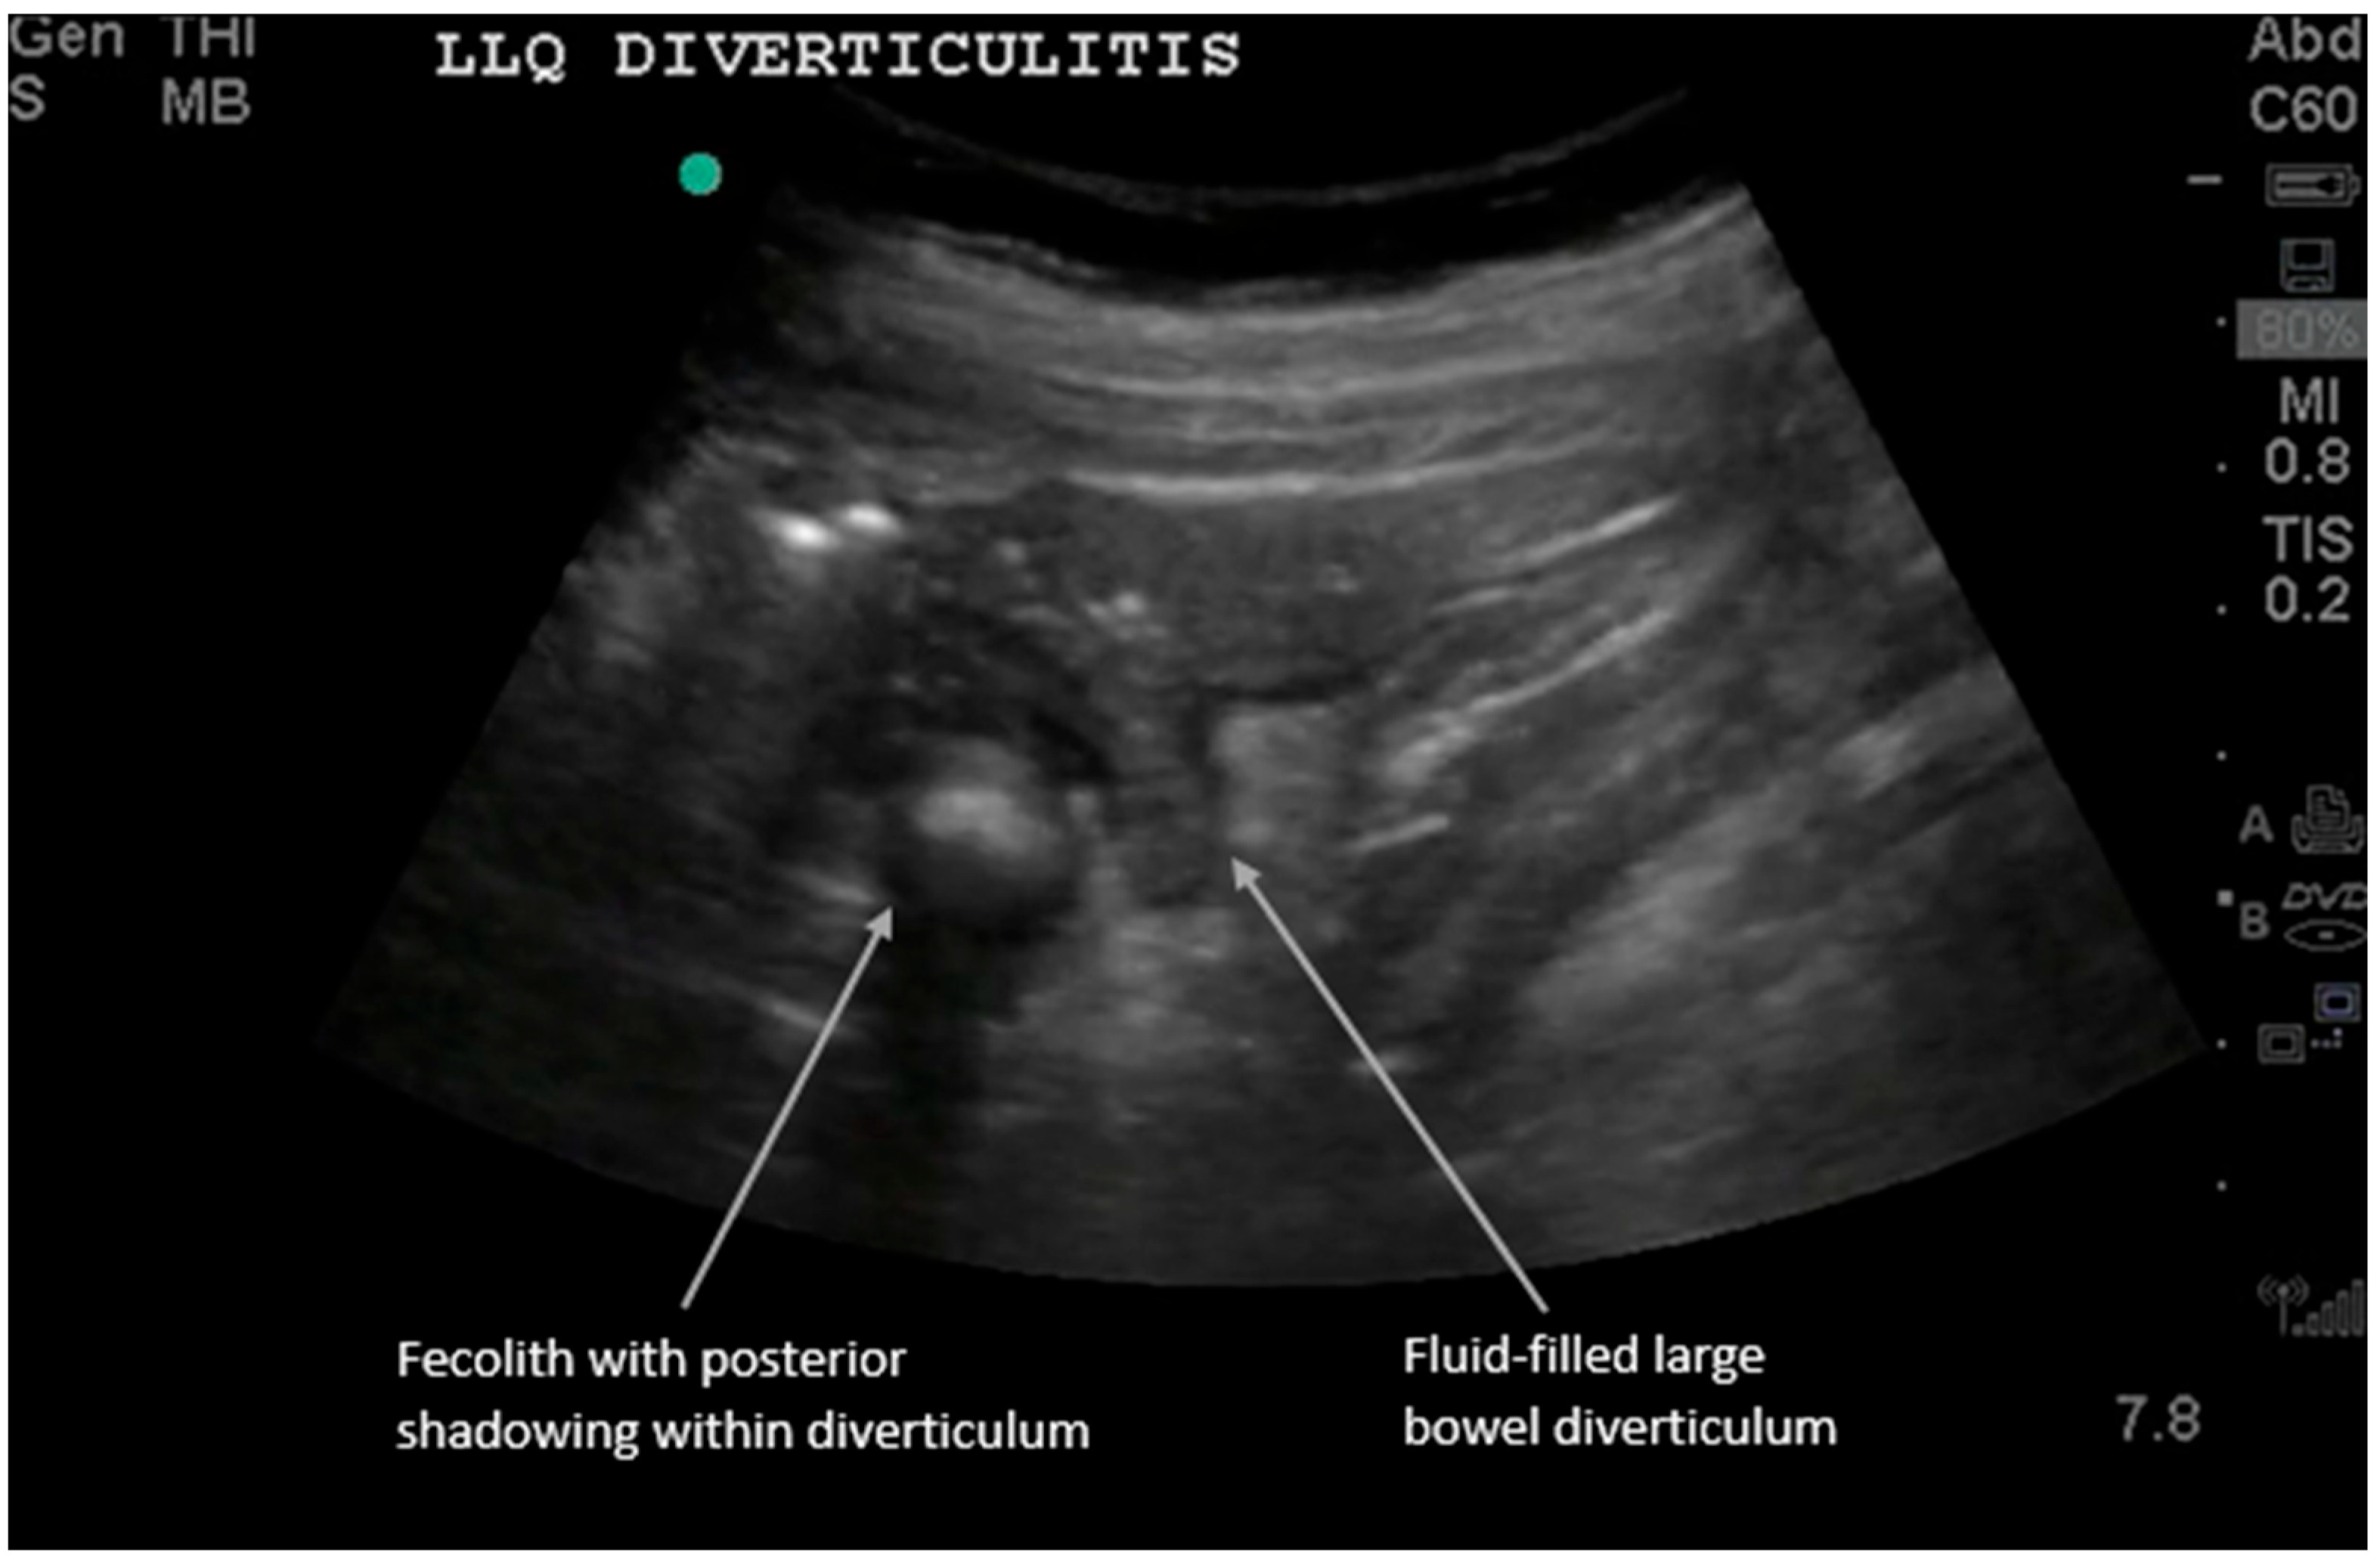

Acute diverticulitis results from inflammation of a colonic diverticulum and most commonly presents with left lower quadrant pain since it typically involves the descending or distal sigmoid colon. The sonographic diagnosis of diverticulitis, as detailed in recent comprehensive reviews, relies on visualizing diverticula as small outpouchings from the colon wall with posterior acoustic shadowing if gas or feces are present [2,5,13,14,15,16]. We present a long-axis view of large bowel diverticulitis, which has the following characteristics on ultrasound: (i) thickened large bowel wall > 5 mm, (ii) hyperemic bowel wall with color Doppler flow mode, (iii) fluid-filled contents in the diverticula, and (iv) non-compressible hyperechoic fat around the bowel. (See Supplementary Video S1 for examples of dynamic findings.) Sometimes the diverticulum can be visualized with a fecolith, and when this obstructs the diverticular neck, it can develop into diverticulitis. Most cases are uncomplicated (85%) and improve with nonoperative antibiotic treatment. However, complicated cases can show adjacent abscesses, fistulas, obstructions, or free air [6,11,12,13,14,15,16,17].